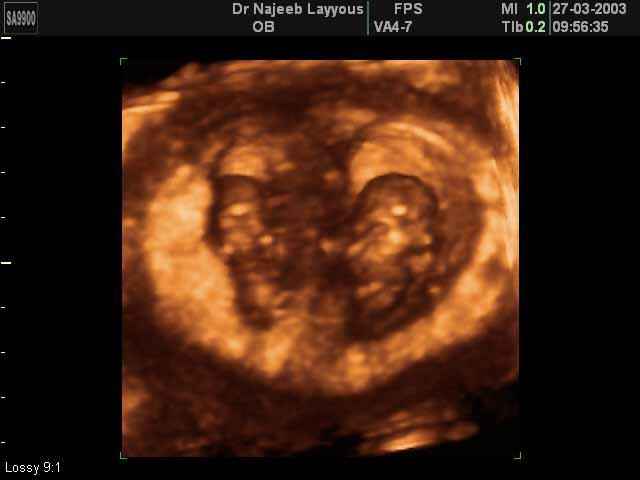

- لقطات فيديو للجنين بجهاز الموجات فوق صوتية رباعي الأبعاد

- صور لتوائم

صور لتوائم بجهاز الالتراساوند ثلاثي الأبعاد | الدكتور نجيب ليوس